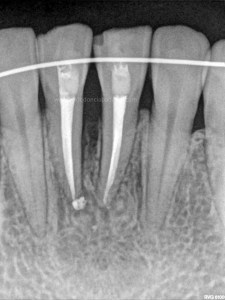

Frente al tratamiento puramente endodóntico, las piezas presentaban vitalidad negativa, fueron tratadas en dos sesiones, rellenando el conducto con Hidróxido de Calcio: